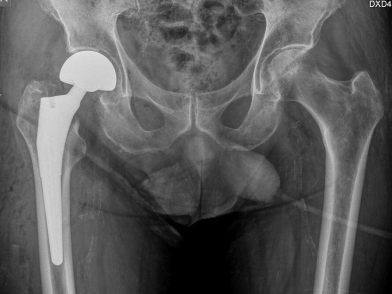

γ) Περιτροχαντήρια κατάγματα. Ανεξαρτήτως ηλικίας η μέθοδος εκλογής είναι η κλειστή ανάταξη και σταθεροποίηση με ενδομυελική ήλωση. Ο ασθενής με γενική ή ραχιαία αναισθησία τοποθετείται σε τραπέζι έλξης και πραγματοποιείται ανάταξη του κατάγματος υπό ακτινοσκοπικό έλεγχο. Το κάταγμα σταθεροποιείται με ενδομυελικό ήλο τύπου γάμμα. Το κύριο στέλεχος του ήλου εισάγεται στον αυλό του μηριαίου οστού από μια οπή στο άνω τμήμα του (μείζονας τροχαντήρας) και σταθεροποιείται με έναν κοχλία που διατρέχει τον αυχένα και την κεφαλή του μηριαίου και έναν κοχλία περιφερικά στη διάφυση του μηριαίου οστού. Σπάνια, μπορεί να επιλεγεί το σύστημα πλάκας – ολισθαίνοντος κοχλία ή η ολική αρθροπλαστική του ισχίου σε ιδιαίτερα συντριπτικά κατάγματα.

Η γρήγορη αντιμετώπιση και η ταχεία έναρξη του προγράμματος αποκατάστασης μετά από ένα κάταγμα ισχίου είναι ύψιστης σημασίας για την καλή έκβαση. Οι ασθενείς είναι πολλές φορές ηλικιωμένοι και έχουν κι άλλα σημαντικά προβλήματα υγείας. Η γρήγορη κινητοποίηση μειώνει τον κίνδυνο σοβαρών επιπλοκών, όπως η θρόμβωση, η πνευμονία, η καρδιακή κάμψη κτλ. Οι ασθενείς με περιτροχαντήρια κατάγματα και υποκεφαλικά κατάγματα που έχουν αντιμετωπιστεί με κοχλίωση ακολουθούν τις περισσότερες φορές πρόγραμμα αποκατάστασης διάρκειας έξι εβδομάδων. Οι ασθενείς που έχουν υποβληθεί σε ημιαρθροπλαστική ή ολική αρθροπλαστική ισχίου έχουν πιο γρήγορη αποκατάσταση. Ιδιαίτερα δε, αν χειρουργηθούν με τη μέθοδο ASI δεν χρειάζεται φυσικοθεραπεία.